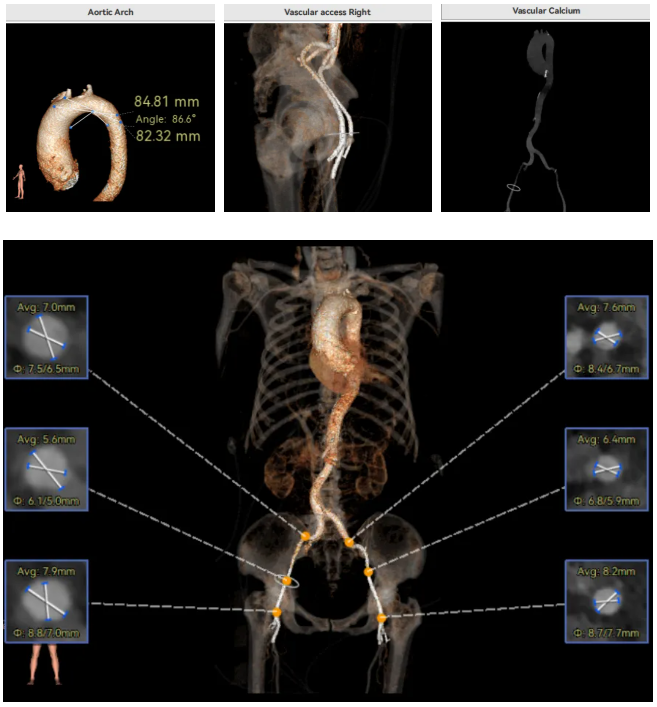

Type1型二叶瓣,L-R融合,瓣叶轻度钙化,主要分布在无窦瓣叶边缘处,主动脉瓣环径23.6mm,LVOT20.6mm,呈收口型;双侧冠脉开口高度可,窦部空间大,VTC距离够,预估冠脉低风险,STJ、升主动脉内径增宽。右冠起源于左窦;主动脉水平夹角65.6°,横位心,主动脉弓角、弓距可。外周入路无明显迂曲,无明显钙化,双侧股动脉内径可,均能通过20F大鞘,右股低分叉。

推荐右侧股动脉为主入路,左侧股动脉为辅助入路,使用20F大鞘,推荐选择AV26瓣膜,备AV23瓣膜,18mm球囊预扩/不预扩,最终理想位置瓣下2mm。